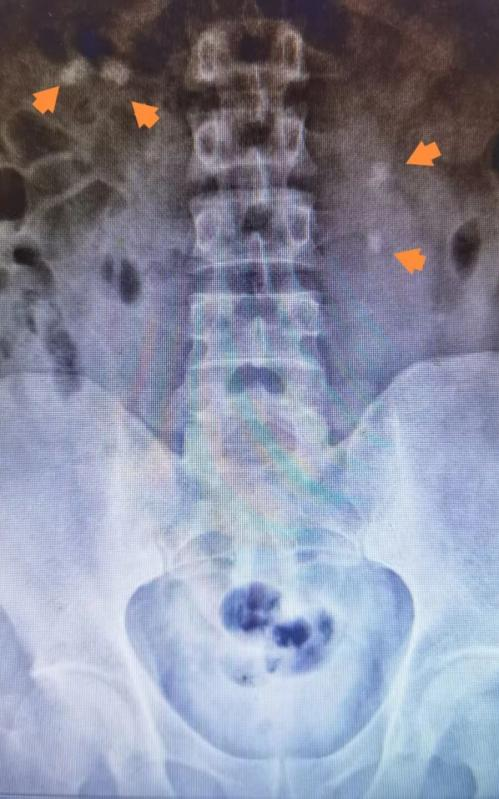

术前与术后对比

自我院引进该技术以来,已在一年内成功为数百例患者解除了结石困扰,其中不乏高难度的双侧结石病例,获得了患者们的一致好评。